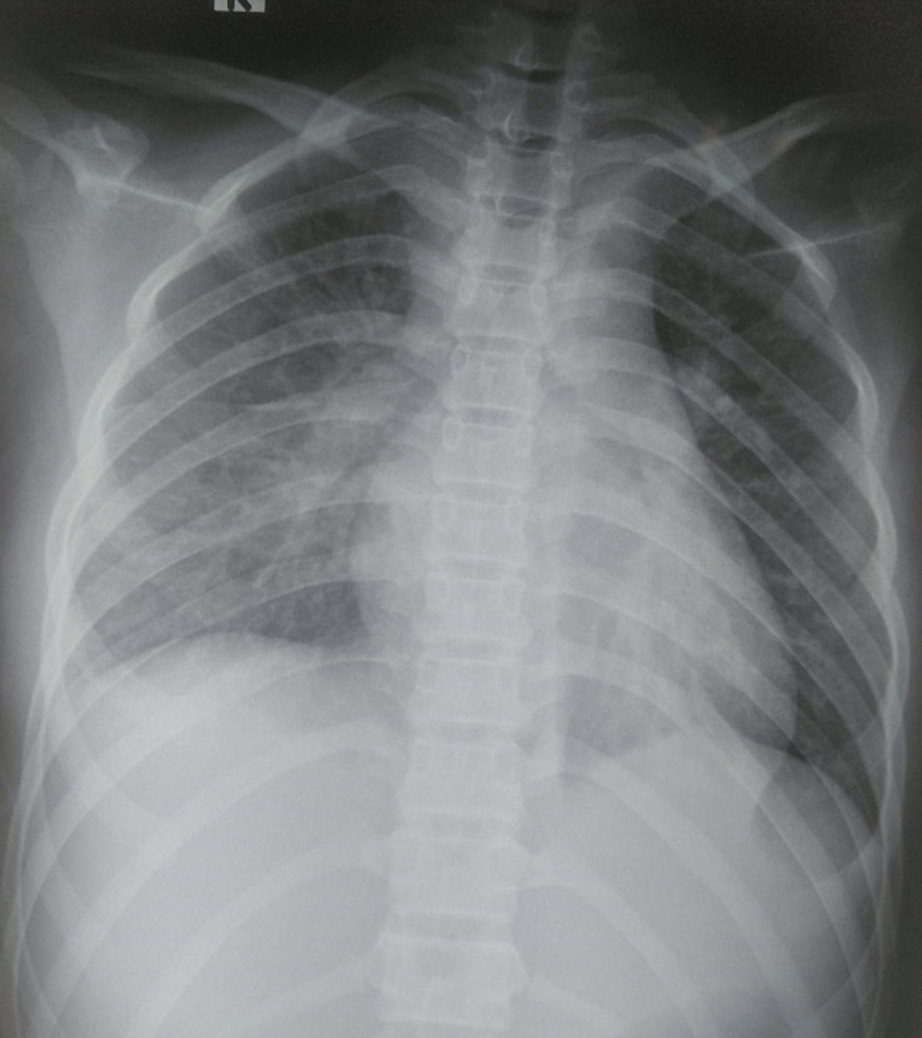

Hình ảnh tổn thương phổi của bệnh nhi trên X-quang. Ảnh: Bệnh viện cung cấp.

Tại bệnh viện, các bác sĩ xét nghiệm phát hiện bệnh nhi bị tổn thương nhiều cơ quan. Cụ thể, phổi tổn thương mờ dạng kẽ vùng rốn phổi 2 bên, tràn dịch màng ngoài tim, tăng chỉ số Troponin T, pro-BNP. Các chỉ số men gan ASAT/ALAT tăng gấp 2 lần, bạch cầu tăng 19 G/L, CRP trên 200 mg/L, định lượng Interleukin-6 (cytokine viêm) tăng cao.